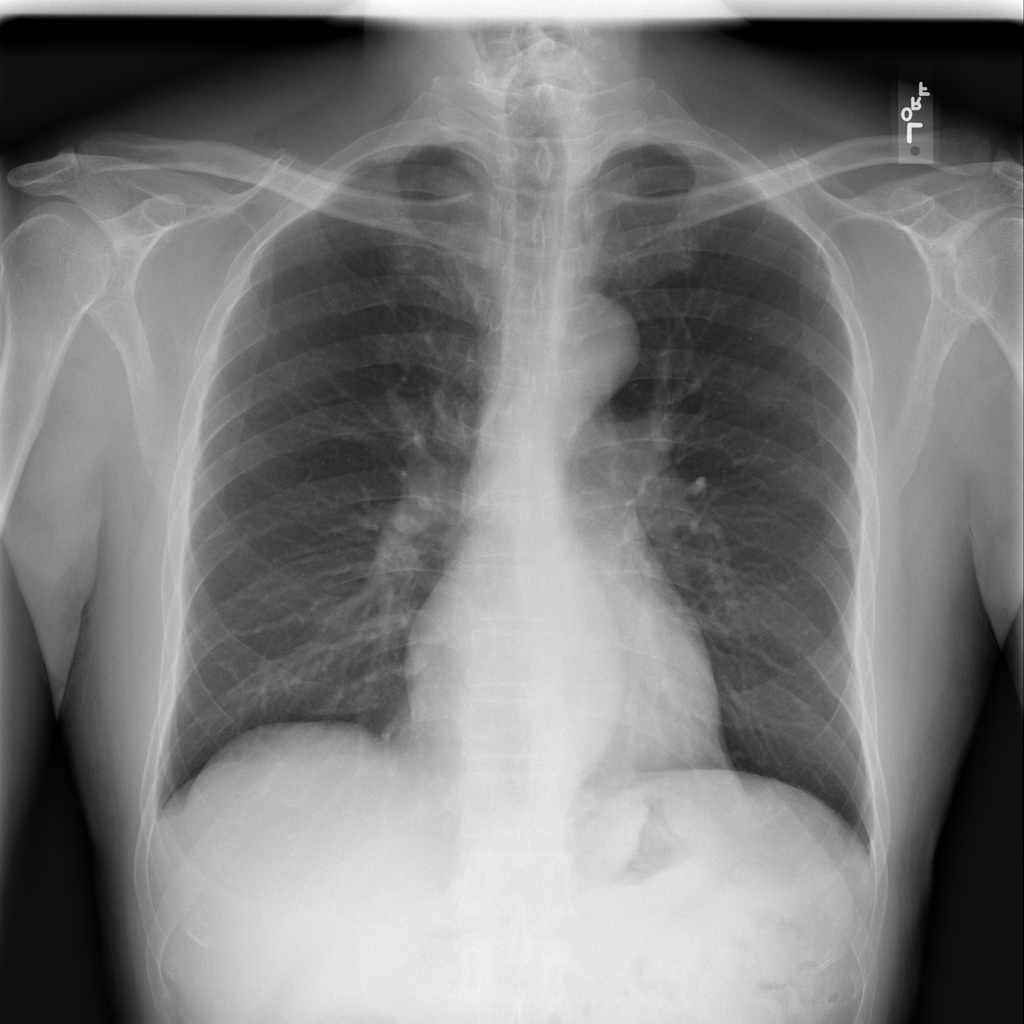

PAT-0ABD · IMG-000Hernia

PAT-0ABD · IMG-000

PA